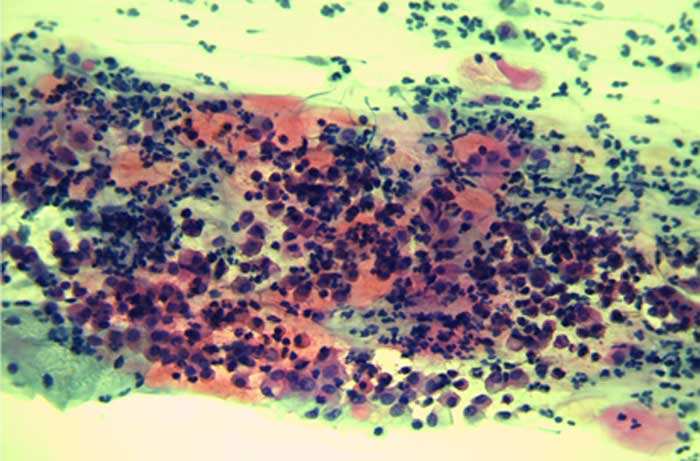

Abstrich Befunde und Pap-Gruppen: Die Unterteilung in Pap-Gruppen gibt Aufschluss über unauffällige Befunde, auffällige Befunde und unklare Befunde. Um einen Befund zu erstellen werden über 100.000 Zellen nach Auffälligkeiten untersucht.

Birgit, 41 J, Gärtnerin, Kinderwunsch, regelmäßige Vorsorge mit unauffälligen Befunden (Pap I) bis 2018, Februar 2019 gleich schwere Krebsvorstufe (Pap IV a). März 2019 Kolposkopie, Gewebeentnahme und HPV-Test mit nachgewiesener Infektion der HPV-Tpen 33 und 59. Befund der Gewebeentnahme bestätigt schwere Krebsvorstufe (CIN III).

Mai 2019 Konisation beseitigt Vorstufen, die Risiken bei zukünftigen Vorsorgen und die Frühgeburtlichkeit werden dadurch deutlich erhöht.